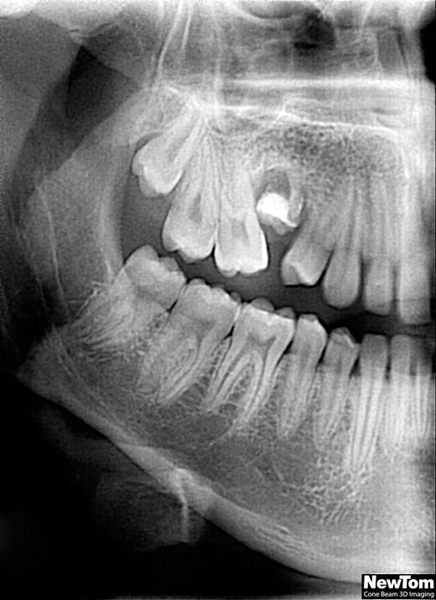

Zuby moudrosti (lidově „osmičky“) se zakládají v čelistech jako poslední zuby kolem 8. roku života a zpravidla prořezávají do dutiny ústní po 17. roce života. Proto velice často není místo pro jejich zařazení do správné polohy a zůstávají částečně nebo úplně skryté v kosti. Mohou být různě skloněné či zdeformované. Dále mohou nepříznivě působit i na sousední zuby či okolní měkké tkáně kolem čelistí jako bolestivý zánět.